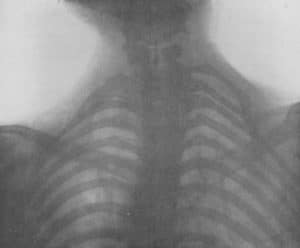

1895

Wilhelm Conrad Roentgen

In 1895, Wilhelm Conrad Röntgen was working with cathode ray tubes when he discovered a novel type of electromagnetic radiation, which he called an “x-ray.” He noted that his body cast a strange image when he passed between the cathode ray tube and a barium-coated screen. After two weeks of experimentation, Röntgen created the first radiograph or roentgenogram. This famous image shows his wife’s hand with a ring. The x-ray enabled doctors (and others) to see inside the living human for the first time, and became an international sensation. X-rays were used for many purposes, and in the setting of TOS made the diagnosis of cervical ribs easy and accurate. These images were known as ‘skiagrams,’ and became a standard part of the workup of patients presenting with vascular compression or aneurysm in the thoracic outlet.

Cervical Rib Syndromes without a Cervical Rib

After the advent of the medical x-ray, physicians thought they had solved the problem of the cervical rib syndrome. Patients with vascular or neurologic symptoms underwent an x-ray examination, and a cervical rib appeared. Shortly after this issue had resolved, a number of reports arose in the medical literature regarding patients with cervical rib syndrome, in whom x-rays demonstrated no cervical rib. Now these same physicians found they faced an entirely new challenge-‘cervical rib syndrome without a cervical rib’ syndrome.